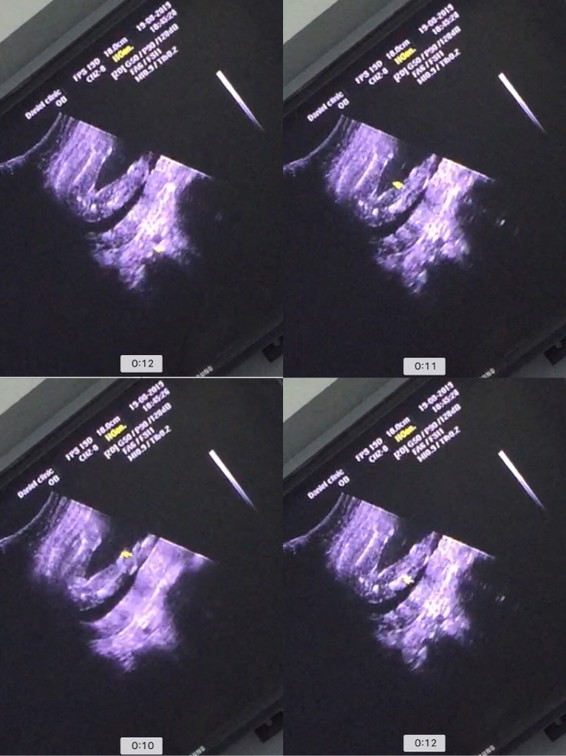

อัลตราซาวด์

20w สามารถอัลตราซาวด์เพศได้รึยังค่ะ จะรู้ชัดหรือยัง ว่า ช.หรือ ญ.

เห็นตั้งแต่ 16wเลยค่ะถ้าน้องเปิดเผย

ถ้าน้องไม่หนีบก็เห็นแล้วค่ะ

บ้านนี้19wค่ะ น้องอ้าขาเลย